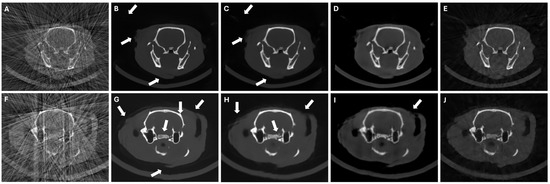

3.3. Results in Conventional Scenarios